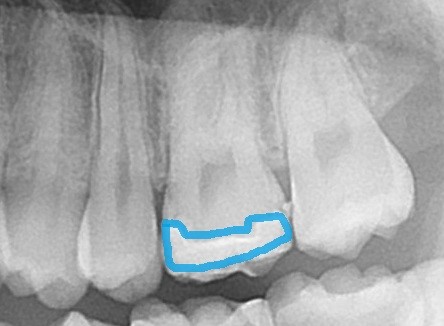

青で示したところがセラミックです。

セラミックはレントゲンで薄く白く写ります。